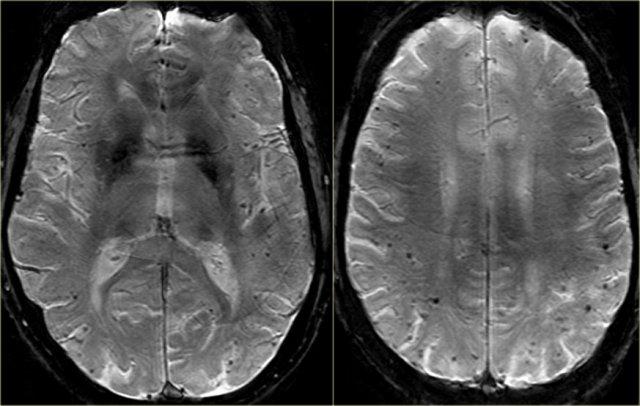

Trên MRI, tăng tín hiệu chất trắng (WMH) và ổ khuyết – cả hai đều thường gặp ở người cao tuổi – thường được xem là bằng chứng của bệnh lý mạch máu nhỏ.

Thang điểm Fazekas cung cấp đánh giá tổng thể về sự hiện diện của WMH trên toàn bộ não.

Thang điểm này được đánh giá tốt nhất trên chuỗi xung FLAIR hoặc T2W mặt phẳng axial.

Điểm số:

- Fazekas 0: Không có hoặc chỉ có một tổn thương WMH dạng chấm đơn độc

- Fazekas 1: Nhiều tổn thương dạng chấm

- Fazekas 2: Bắt đầu hợp lưu các tổn thương (cầu nối)

- Fazekas 3: Tổn thương hợp lưu diện rộng

Thang điểm Fazekas đánh giá tổn thương chất trắng dự báo tình trạng tàn tật trong tương lai ở người cao tuổi.

Fazekas 1 được coi là bình thường ở người cao tuổi.

Fazekas 2 và 3 là bệnh lý, nhưng có thể gặp ở những cá nhân có chức năng bình thường.

Tuy nhiên, những đối tượng này có nguy cơ cao bị tàn tật.

Trong một nghiên cứu trên 600 người cao tuổi có chức năng bình thường, điểm Fazekas dự báo tình trạng tàn tật trong vòng một năm (bảng). Trong nhóm Fazekas 3, 25% bị tàn tật trong vòng một năm (10).

Bên trái là hình ảnh của một bệnh nhân được chẩn đoán VaD.

Bệnh lý chất trắng được thấy dưới dạng tăng tín hiệu chất trắng nặng nề (giảm tín hiệu trên T1W) ở vùng quanh não thất.

Ngoài các thay đổi mạch máu này, còn có MTA.

Có thể bệnh nhân này mắc cả VaD và AD, một phát hiện thường gặp ở nhiều bệnh nhân cao tuổi.

Các dấu hiệu này cần được mô tả riêng biệt vì có thể có hệ quả điều trị.

Tuy nhiên, vấn đề là tăng tín hiệu chất trắng và ổ khuyết cũng thường được quan sát thấy ở người cao tuổi không sa sút trí tuệ và ở một mức độ nào đó có thể được coi là dấu hiệu bình thường trong quá trình lão hóa.